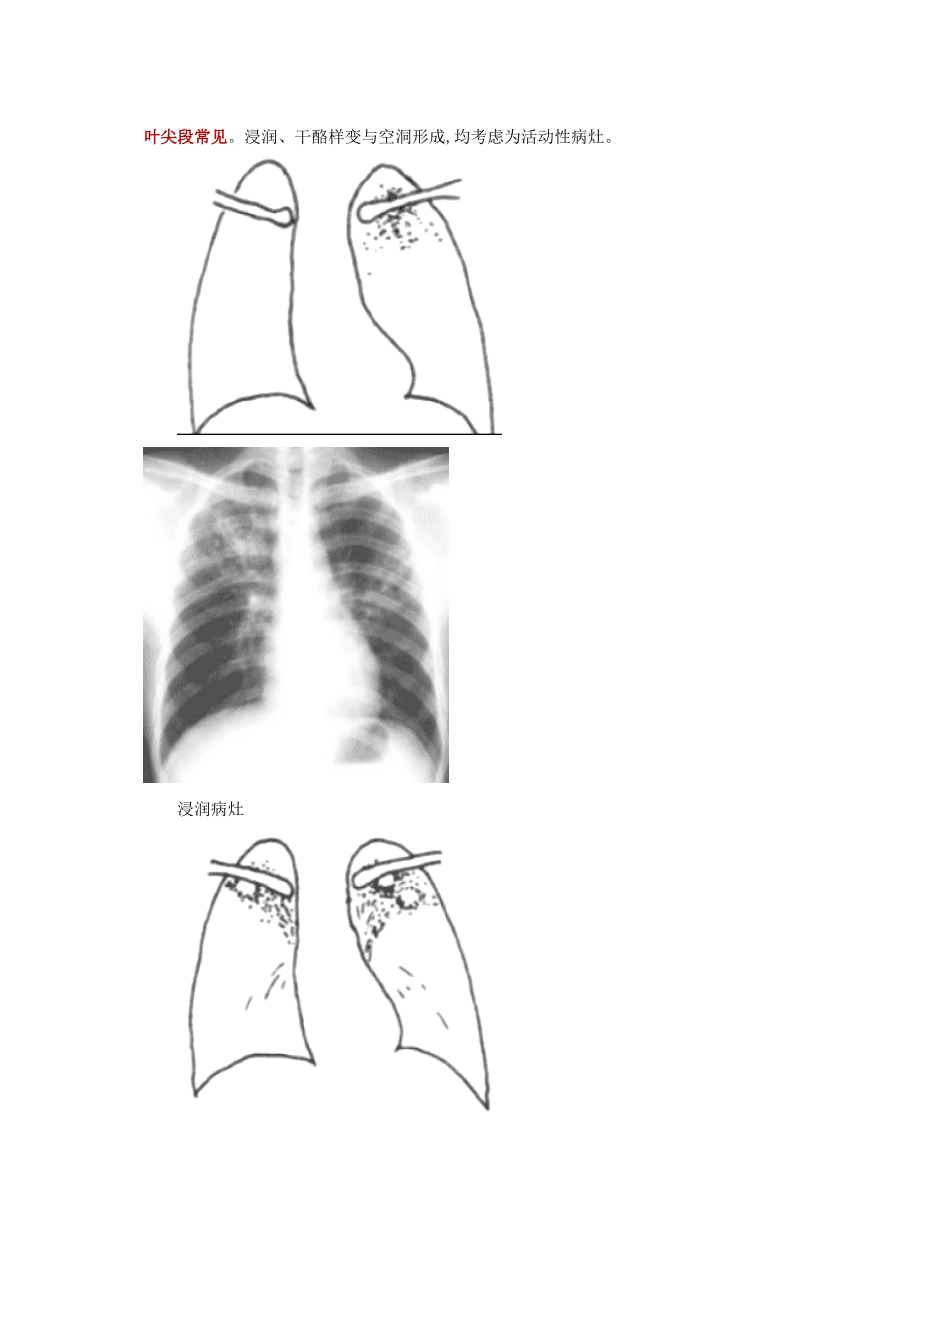

第三章 病例分析——结核病 一、概述 1、概念 结核病就是结核分枝杆菌引起得慢性传染病,可侵及多个脏器,以肺部受累形成肺结核最为常见。 痰中带菌者称为传染性肺结核,传染性肺结核病人排菌就是结核传播得主要来源,主要为病人与健康人之间经飞沫传播。人体感染结核杆菌后不一定发病,当抵抗力降低时,才会引起发病。 其病理变化为渗出型、增生型、干酪样坏死三种类型。三种病变可以相互转化、交错存在,很少单一病变独立存在,而以某一种改变为主。 2、结核病分型 Ⅰ型:原发型肺结核,多见于儿童,典型病变包括肺部原发灶,引流淋巴管与肺门淋巴结得结核性炎症,三者联合称为原发综合征。多数原发综合征临床症状轻微,不治自愈,很少排菌。 Ⅱ型:血行播散型肺结核,儿童多来源于原发性肺结核;成人多由原发感染灶中得结核菌破溃进入血行引起。本型肺结核发生于免疫力极度低下者。 Ⅲ型:继发型肺结核,为成人与继发性肺结核最常见类型。好发于两肺上叶尖后段或下叶尖段,病灶趋于局限,易于有干酪坏死与空洞形成,排菌较多。 Ⅳ型:结核性胸膜炎:常见胸腔积液,为渗出液,草绿色,淋巴细胞为主,ADA 明显升高。 V 型:其她肺外结核 二、诊断要点 1、全身症状:发热,多数为长期低热,,可伴有倦怠、乏力、夜间盗汗、食欲减退、体重减轻、妇女月经不调、易激惹、心悸、面颊潮红等。 2、呼吸道症状:咳嗽、咳痰、咯血、胸痛、呼吸困难。 3、体征: 病灶以渗出型病变为主得肺实变且范围较广或干酪性肺炎时,叩诊浊音,听诊闻及支气管呼吸音与细湿啰音。 继发型肺结核好发于上叶尖后段,故听诊于肩胛间区闻及细湿啰音,有极大提示诊断价值。 空洞性病变位置浅表而引流支气管通畅时有支气管呼吸音或伴湿啰音;巨大空洞可出现带金属调得空瓮音。 慢性纤维空洞性肺结核得体征有患侧胸廓塌陷、气管与纵隔间向患侧移位、叩诊音浊、听诊呼吸音降低或闻及湿啰音,以及肺气肿征象。 支气管结核有局限性哮鸣音,特别就是于呼气或咳嗽末。 4、实验室与辅助检查 1)病原学检查 ① 痰涂片 抗酸染色直接镜检有助于诊断 ② 痰培育 具有较高得敏感性与特异性 ③ 结核菌抗原与抗体检测 2)影像学检查 ① X 线胸片 原发性肺结核典型特征有原发灶、淋巴管炎与肺门或纵隔肿大得淋巴结组成哑铃状病灶。 急性血行播散型肺结核在 X 线胸片上呈现分布均匀、大小密度相近得粟粒状阴影。 继发型肺结核得常见 X 线表现包括浸润性病灶,如云雾状,边缘模糊,密度相对较淡;干酪样...